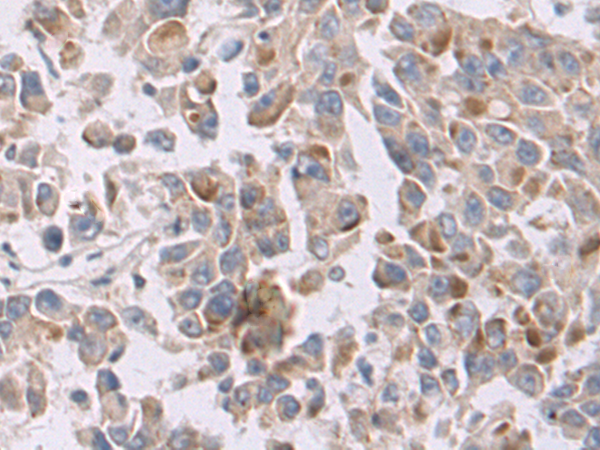

分类: 科研抗体货号: P11638别名: CD327; CD33L; OBBP1; CD33L1; CD33L2; CDW327应用: WB,IHC反应种属: Human